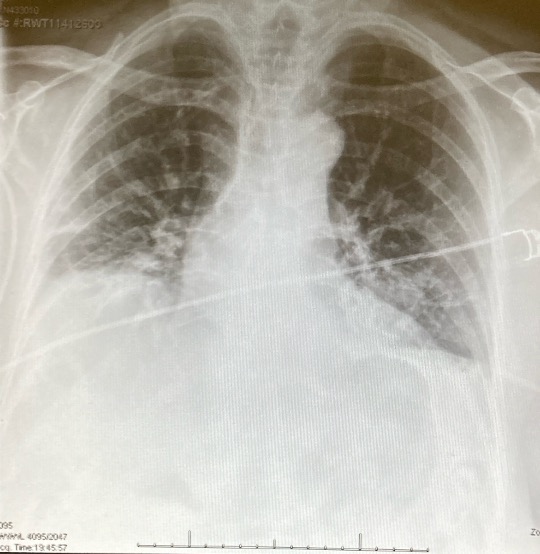

Postoperatively, the chest drain was removed at six hours (Figure 5), and the patient was discharged 20 hours after the operation on postoperative day one (Figure 6). The patient experienced no postoperative complications and had an uneventful postoperative recovery.

Figure 6: An image of the postoperative CXR with the drain out.

Histopathological analysis confirmed the lesion as a metastatic deposit from the patient’s primary breast adenocarcinoma, which was diagnosed 11 years prior. Complete resection with clear margins was achieved.